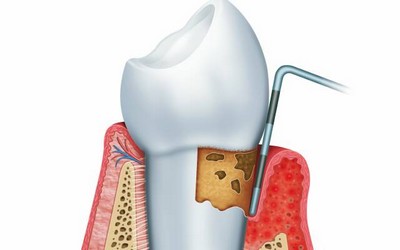

Из перечисленных выше действий к первичной диагностике относится пальпация тканей и зондирование. С помощью этих процедур врач определяет наличие воспаления. Все остальные действия относятся к дополнительным методам.

Поэтому хирургический способ используется врачами в тех ситуациях, когда консервативный уже не поможет. Назначается он в следующих случаях:

Если нет возможности провести такие манипуляции с зубом, то проводят лечение хирургическим способом: делают местную анестезию, удаляют инфицированную верхушку зуба, делают ретроградное пломбирование корневого канала, затем вокруг корня укладывают искусственную костную ткань, устанавливают мембрану и укладывается назад десневой лоскут.

Если периодонтит сопровождается припухлостью десны, то необходимо провести вскрытие гнойного абсцесса, разрезав десну.